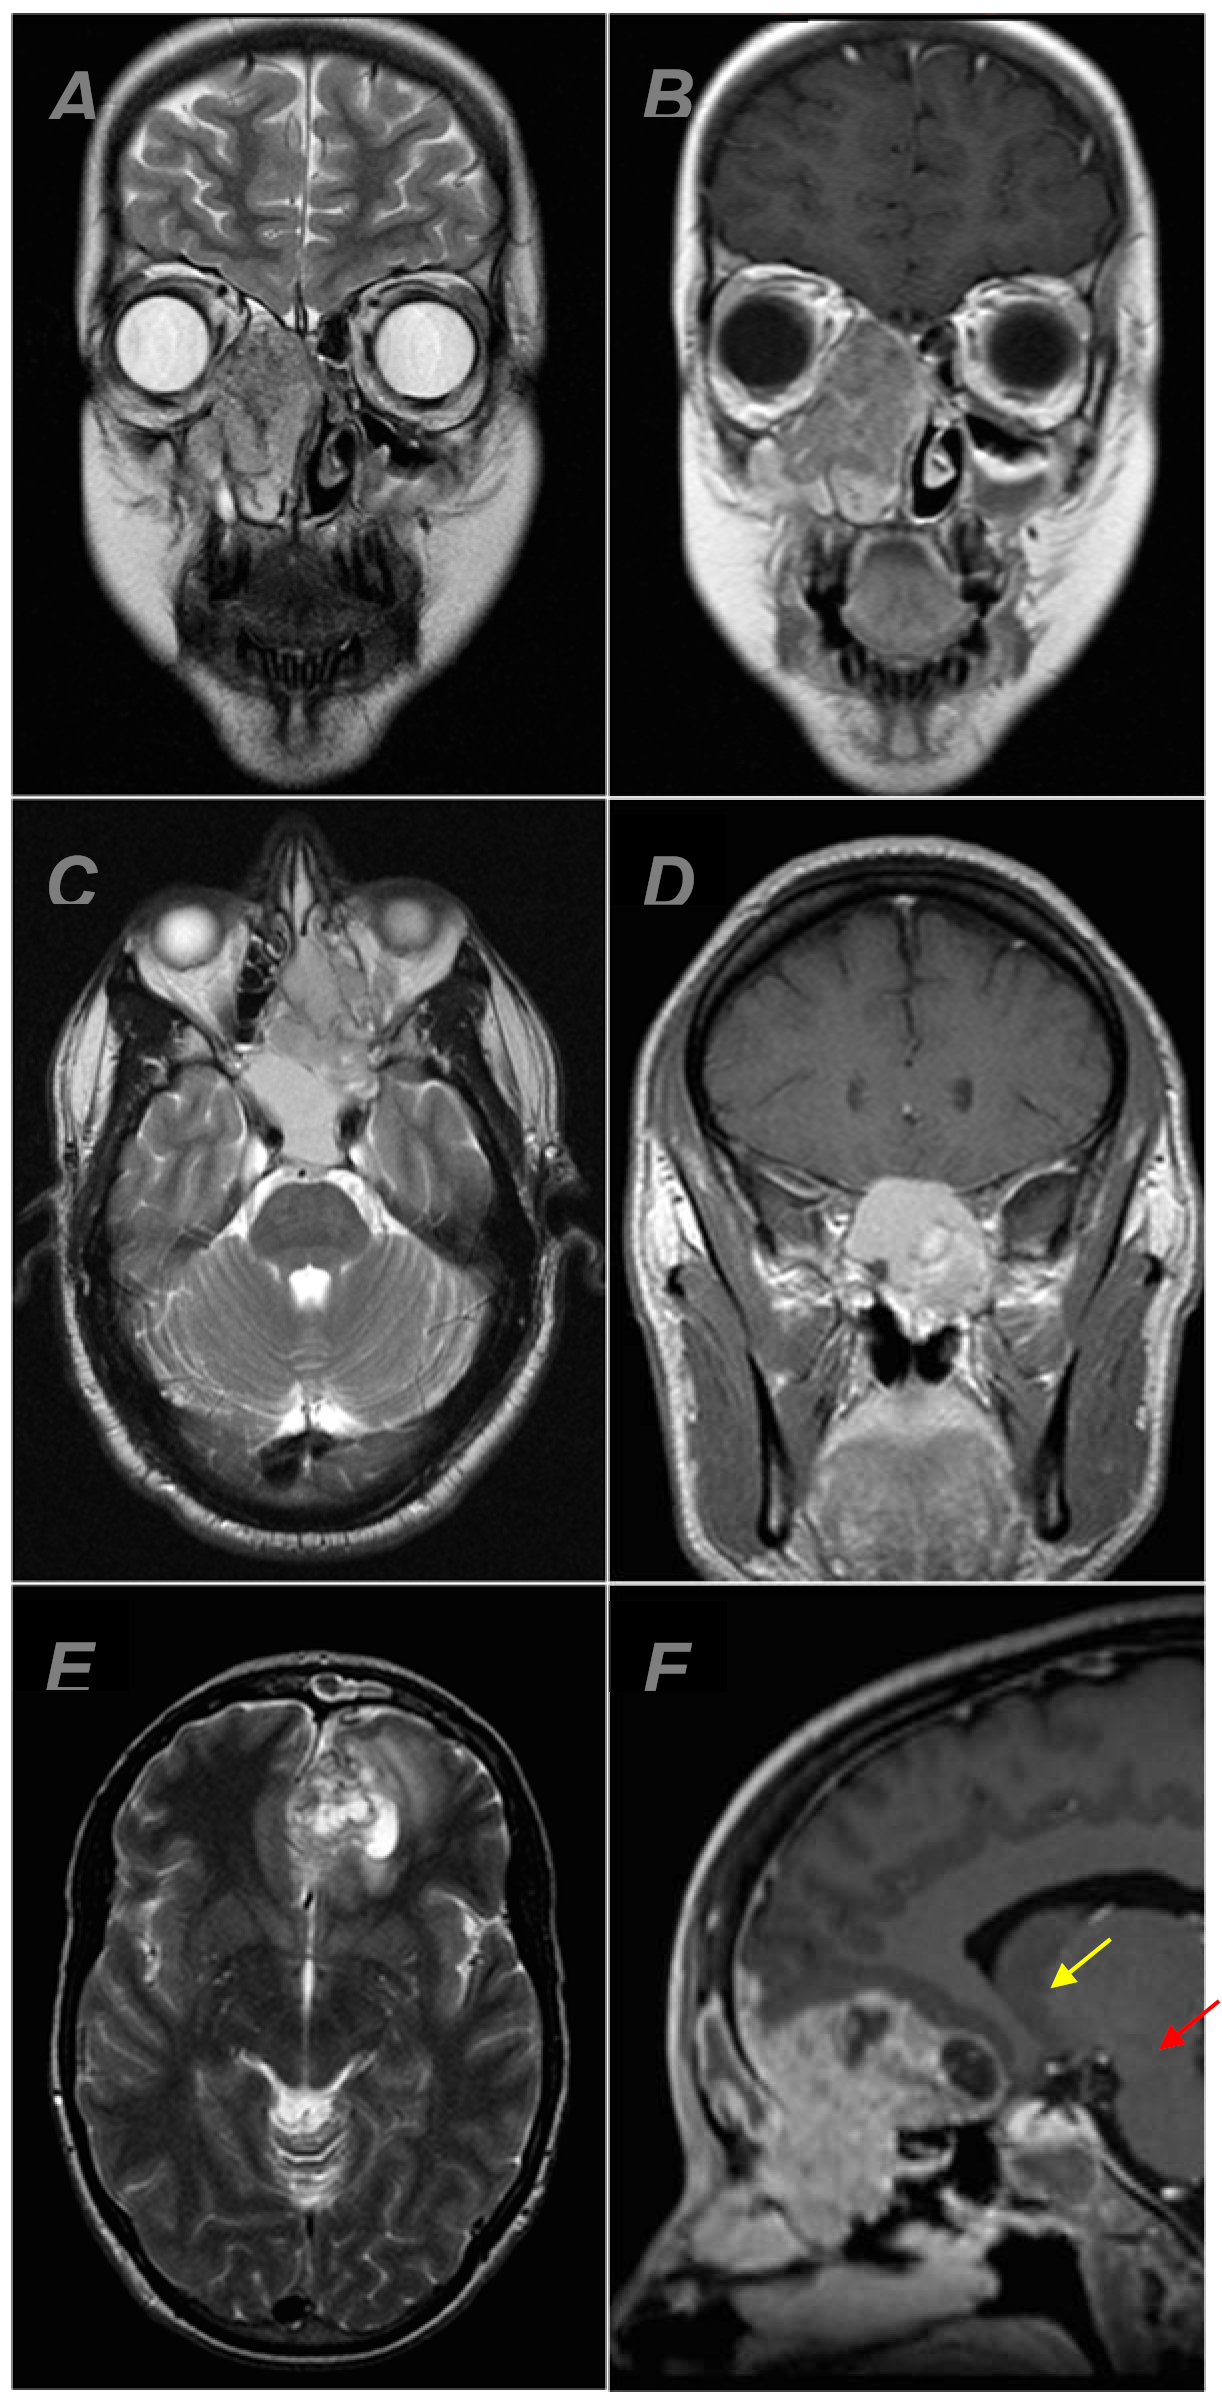

Olfactory Neuroblastoma: Re-Evaluating the Paradigm of Intracranial Extension and Cyst Formation

| Intracranial extension | yes | 18 (58.1%) |

| Cyst formation | yes | 4 (22.2%) |